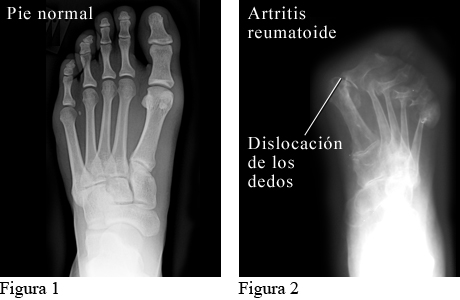

Figura 1 cortesía de Intermountain Medical Imaging, Boise, Idaho. Figura 2 cortesía de Paul Traughber, MD, Boise, Idaho.

La radiografía de la izquierda muestra un pie normal.

La radiografía de la derecha muestra un pie con artritis reumatoide avanzada. El cartílago y el hueso se han desgastado y los huesos de los dedos de los pies se han movido de sus posiciones normales.